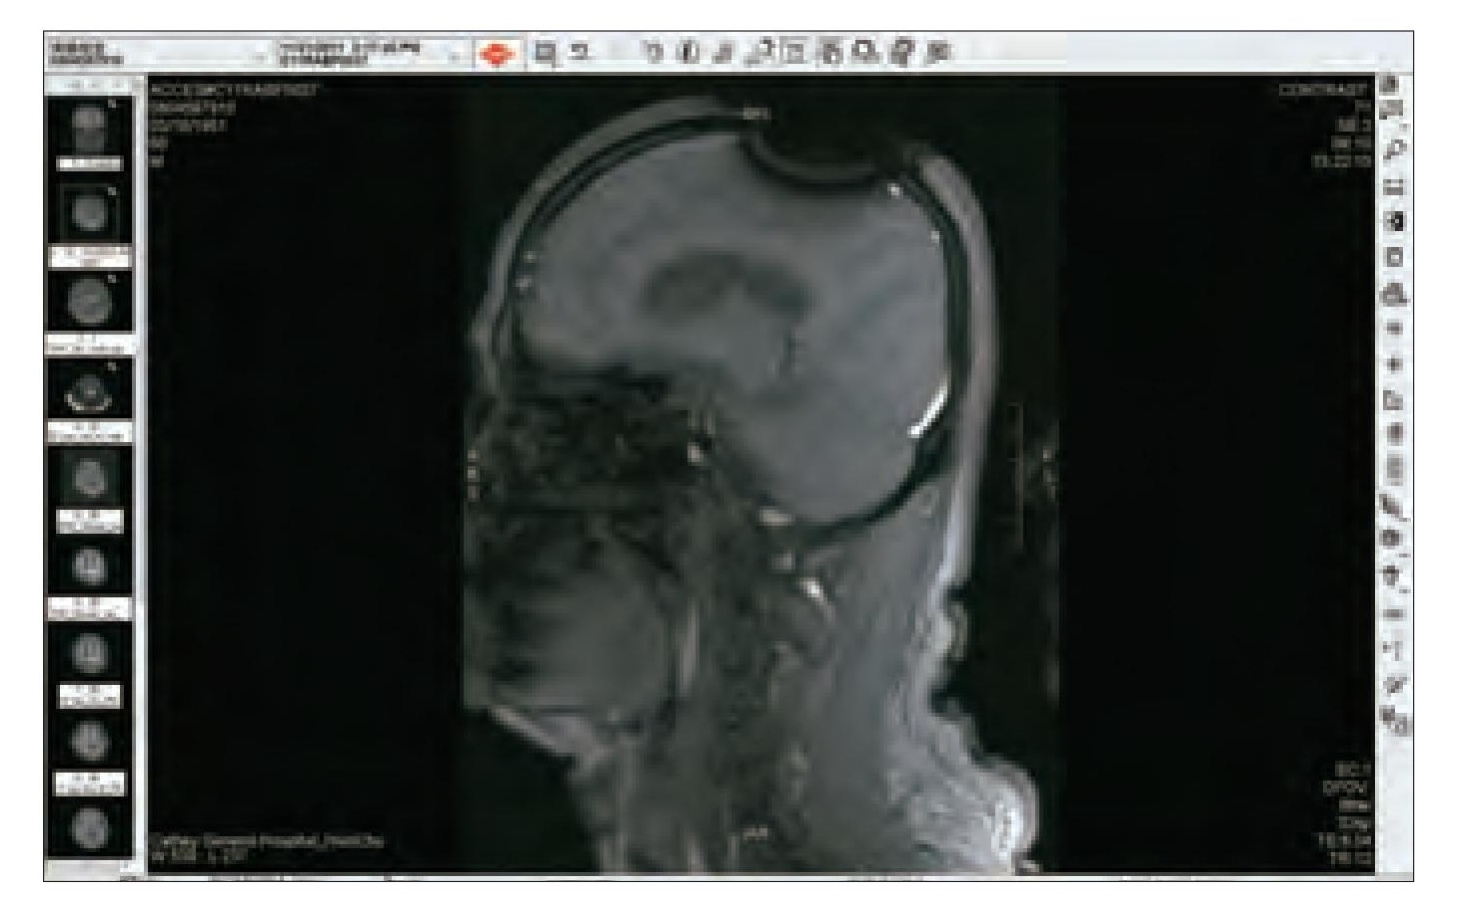

(7) 為什麼不照相或錄影 ??? 再想想, 金剛換體禪並不是開"心", 而是開"頂". 頭頂有沒有打開, 這些法師法王都是光頭或小平頭, 讓人瞧一眼就知道了, 用手機照張相片或錄影就知道了, 何必大費周章, 一群華藏寺法師法王都跑到醫院去照昂貴的MRI呢 ?! 直接證據不用, 卻要用可容造假的間接證據.

(9)"老闆娘, 我也要來一張!"在台灣的健保, 病況需要時每半年可以免費照一張MRI. 所以只要在頭頂上噴灑一些金屬粉末, 並用髮膠固定. 細小的黑粉末是一定可以讓現場醫事檢驗人員既看不出來也摸不出來, 如此就可瞞過醫院. 去看醫生時就說頭內部很不舒服. 要求要照MRI. 公立醫院通常比較不會輕易讓病人照MRI. 少數私立醫院因為購買MRI機器的成本非常昂貴, 因此比較可能會照MRI, 目的顯然是為了回本.

就這樣, 你幾乎不花一毛錢, 就可以輕易瞞天過海又免費照出並拿到"開頂成聖"的MRI影像圖了. 先讓台灣健保替你付費. 如果你要, 還可在公車火車坦克車上打廣告, 再讓台灣信徒把你當大聖德大法王敬拜供養.